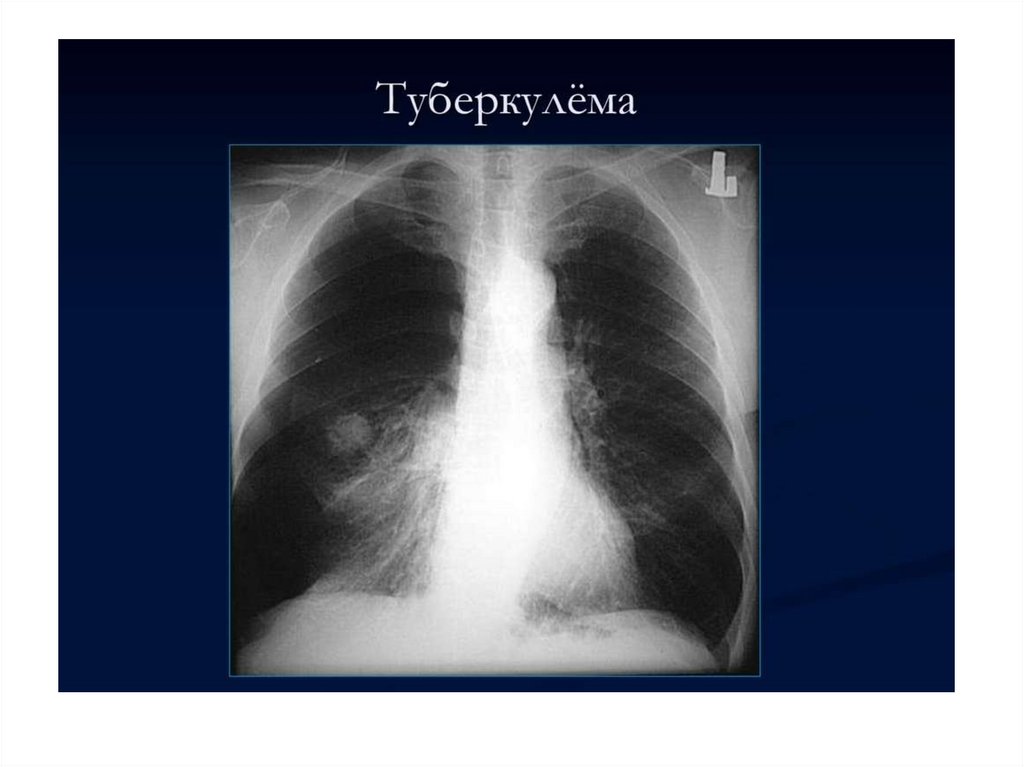

Малые формы туберкулеза легких тренинг по основным малым формам туберкулеза легких

Малые формы туберкулеза легких

тренинг по основным

малым формам туберкулеза легких